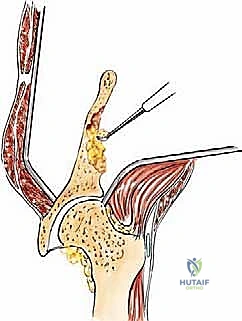

* الخطوات: يتم فتح نافذة في العظم للوصول للورم. يستخدم الجراح أدوات دقيقة لكشط وإزالة أكبر قدر ممكن من النسيج السرطاني (Curettage).

* التدعيم: لقتل أي خلايا سرطانية متبقية مجهرياً ولتعويض الفراغ العظمي، يتم حقن الإسمنت العظمي الطبي (Polymethylmethacrylate - PMMA). يتميز هذا الإسمنت بأنه يتصلب بسرعة ويولد حرارة عالية أثناء التصلب (تصل إلى 80 درجة مئوية)، مما يؤدي إلى "كيّ" الخلايا السرطانية المحيطة (Thermal Necrosis).

* التثبيت: يتم تدعيم الإسمنت باستخدام مسامير معدنية طويلة، شرائح، أو أسياخ معدنية قوية لضمان ثبات الحوض.